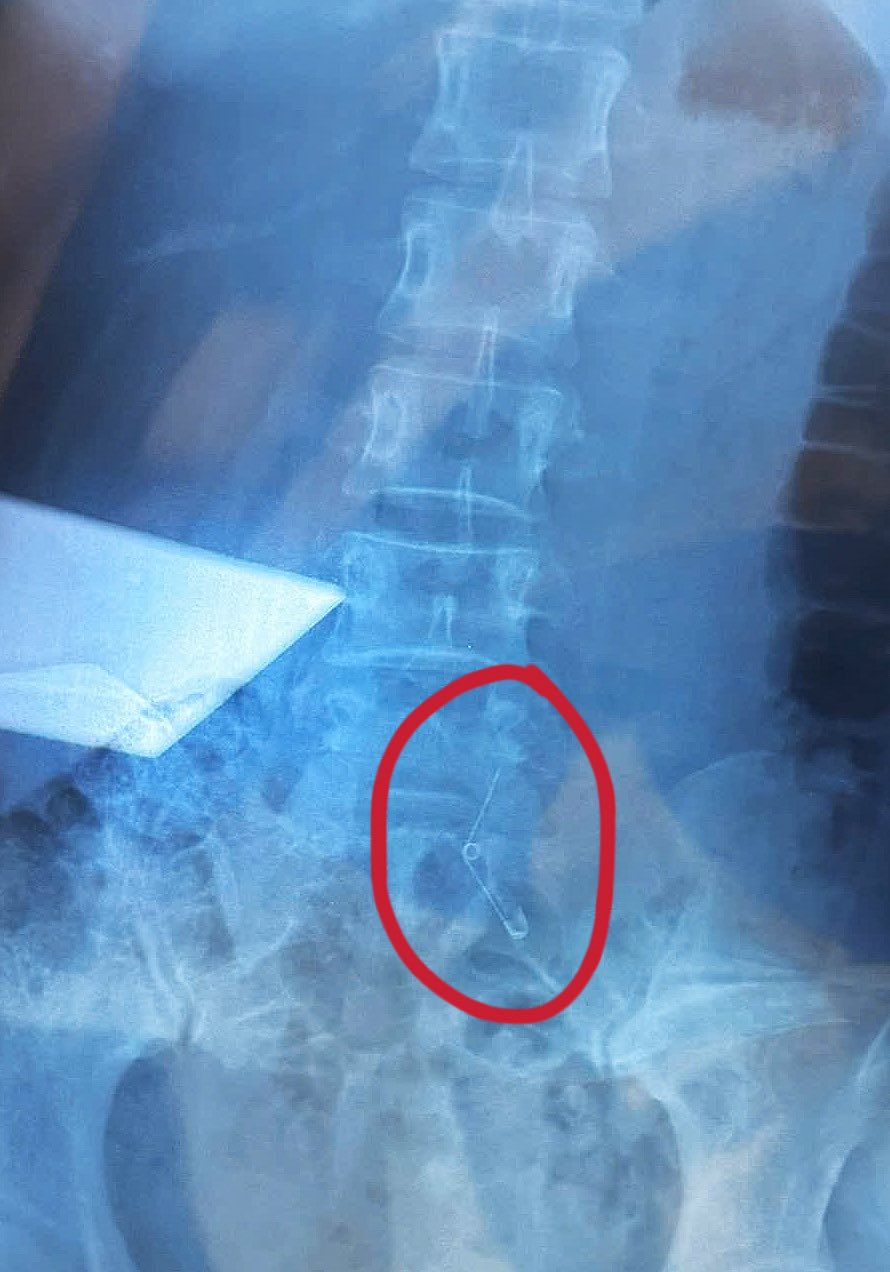

Theo đó, vào tối 26/9, Vân Anh cùng nhân viên công ty ở TP.HCM đi ăn ốc. Đang ăn, cô cảm thấy nuốt nghẹn nghẹn và nhận ra mình không còn cầm kim băng - vật dùng để khều ốc trên tay nữa. Sau đó Vân Anh được đưa đi cấp cứu và mất 6 tiếng để mổ lấy kim băng ra.

Vân Anh Scarlet khi ở bệnh viện và ảnh chụp X-quang chiếc kim băng

Vết mổ và cận cảnh chiếc kim băng sau khi được lấy ra